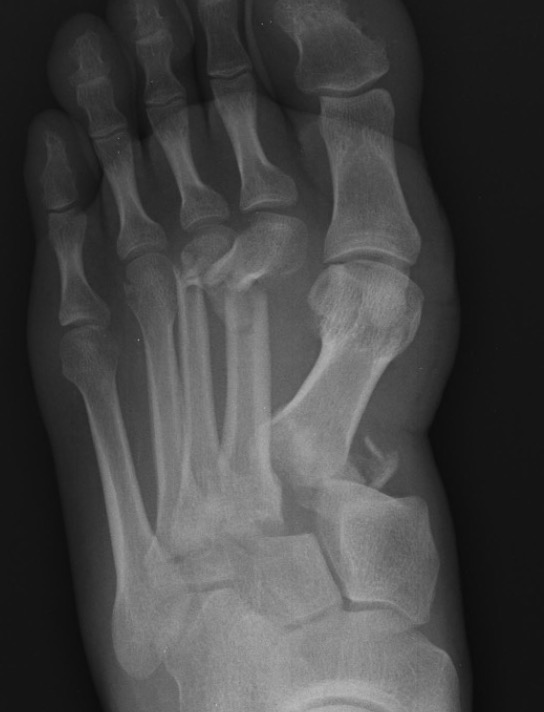

Classification

| Isolated | Homolateral | Divergent |

|---|---|---|

| Only 1st MT injured / displaced | All 5 metatarsals displaced in same direction |

1st metatarsal displaces medially Other 4 metatarsals displace laterally |

| Most common | Least common | |